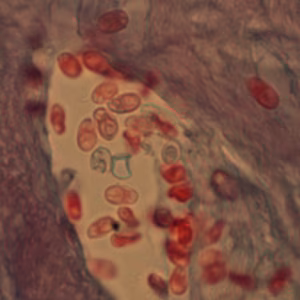

Encephalitozoon cuniculi in urine and kidney biopsy specimens, stained with Ryan’s modified trichrome stain.

Tubulinosema acridophagus in bronchoalveolar lavage (BAL) specimens, stained with Chromotrope 2R stain.

Ocular microsporidiosis stained with trichrome and Giemsa.

Light microscopic examination of the stained clinical smears, especially the fecal samples, is an inexpensive method of diagnosing microsporidial infections even though it does not allow identification of microsporidia to the species level. The most widely used staining technique is the Chromotrope 2R method or its modifications. This technique stains the spore and the spore wall a bright pinkish red. Often, a darker-staining equatorial band is seen in the middle of the spore. This technique, however, is lengthy and time consuming and requires about 90 min. A recently developed “Quick-Hot Gram Chromotrope technique” however, cuts down the staining time to less than 10 min and provides a good differentiation from the lightly stained background fecal materials so that the spores stand out for easy visualization. The spores stain dark violet and the equatorial band is enhanced. In some cases dark staining Gram positive granules are also clearly seen. Chemofluorescent agents such as Calcofluor white are also useful in the quick identification of spores in fecal smears. The spores measure from 0.8 to 1.4 µm in the case of Enterocytozoon bieneusi, and 1.5 to 4 µm in Anncaliia algerae, Encephalitozoon spp., Vittaforma corneae, and Nosema spp.